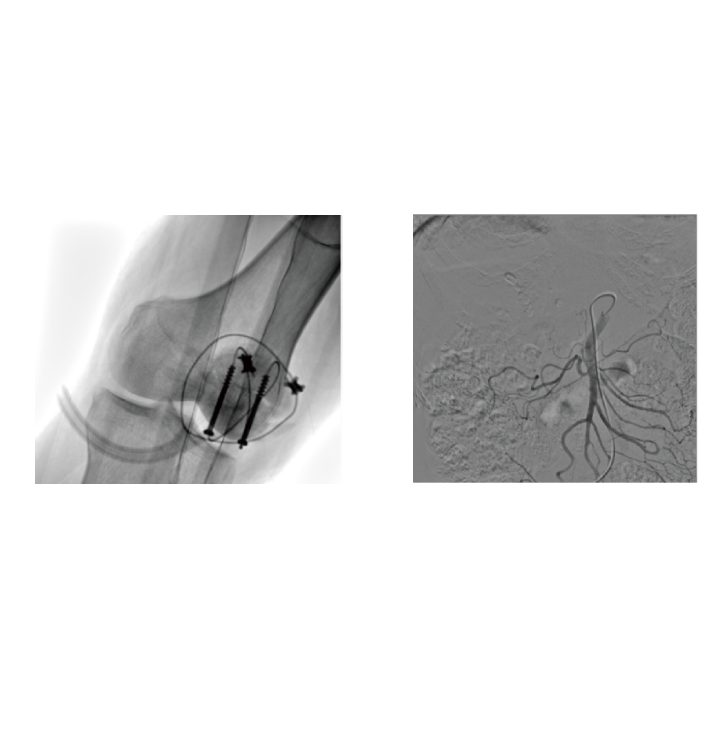

- 25KW high power, breakthroughs in both penetration and clarity.

- Controllable low pulse width and variable intelligent filtration.

- Low-dose technology ensures both safety and image quality.

- 2. 3D Imaging, Stereoscopic Vision:

- Built-in three-dimensional tomography function, which can quickly reconstruct high-resolution stereoscopic images and assist in delicate operations such as pedicle screw placement and complex fracture reduction.

- 3. Comprehensive Coverage of Surgical and Interventional Scenarios

- From orthopedics and trauma surgery to peripheral intervention, it fully supports open surgery and minimally invasive intervention scenarios. One device meets diverse needs and helps hospitals optimize resource allocation.